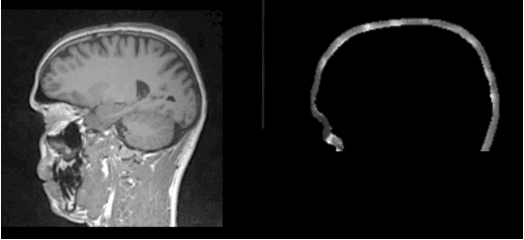

Simultaneous EEG/fMRI acquisition allows to measure brain activity at high spatial-temporal resolution. The localisation of EEG sources depends on several parameters including the position of the electrodes on the scalp. The position of the MR electrodes during its acquisitions is obtained with the use of the UTE sequence allowing their visualisation. The retrieval of the electrodes consists in obtaining the volume where the electrodes are located by applying a sphere detection algorithm. We detect around 90% of electrodes for each subject, and our UTE-based electrode detection showed an average position error of 3.7mm for all subjects.